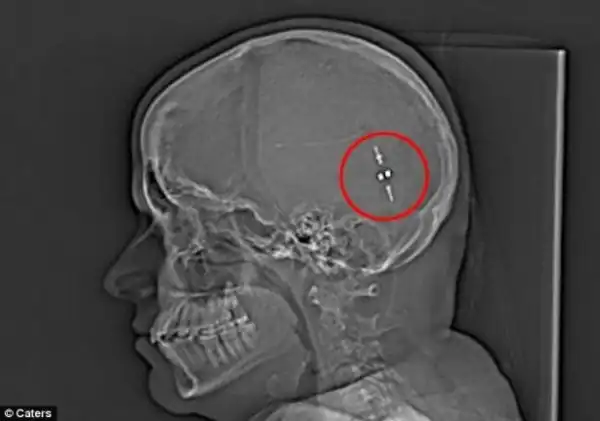

Это приводит к тому, что накапливающаяcя в черепе жидкость, давит на мозг и в крайних случаях это может даже привести к слепоте. Состояние Сэм было настолько тяжелым, что она была прикована к постели и врачи считали, что она была близка к инсульту. Но после того, как они нашли способ удалять избыток жидкости из ее мозга в желудок, ее жизнь изменилась. Слив, также известный, как желудочно-перитонеальный шунт, соединил мозг и желудок, позволяя ей переварить свою мозговую жидкость и снизить давление на мозг.

И только в мае прошлого года девушке был установлен шунт для слива лишней жидкости. Сэм надеялась на немедленное облегчение, но ее мозгу потребовалось время, чтобы привыкнуть к инородному телу. Спустя некоторое время Сэм приспособилась к изменениям и с тех пор она снова живет нормальной жизнью.